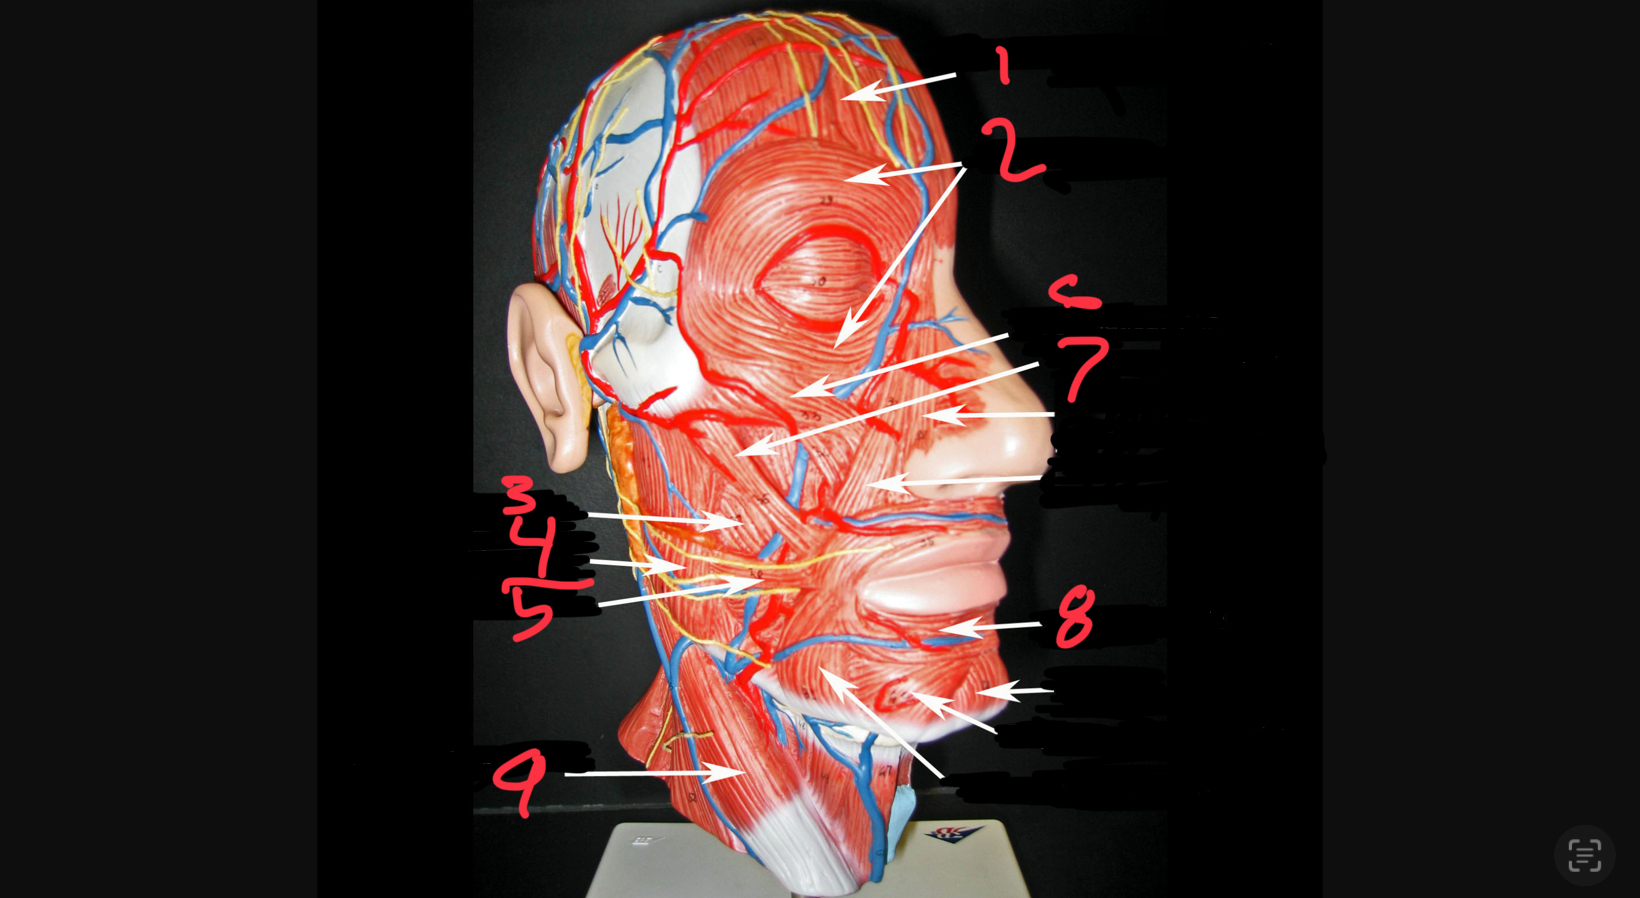

what #1

occipitofrontalis (frontal belly)

what is #2

orbicularis oculi

what is #3

buccinator

what is #4

masseter

what is #5

risorius

what is #6

zygomaticus minor

what is #7

zygomaticus major

what is #8

orbicularis oris

what is #9

sternocleidomastoid